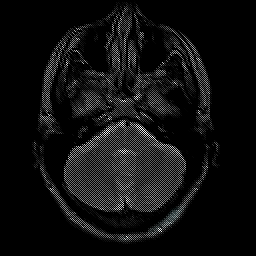

Glioma overlay -- Slice #6

[Home][Help][Clinical] Slice 6